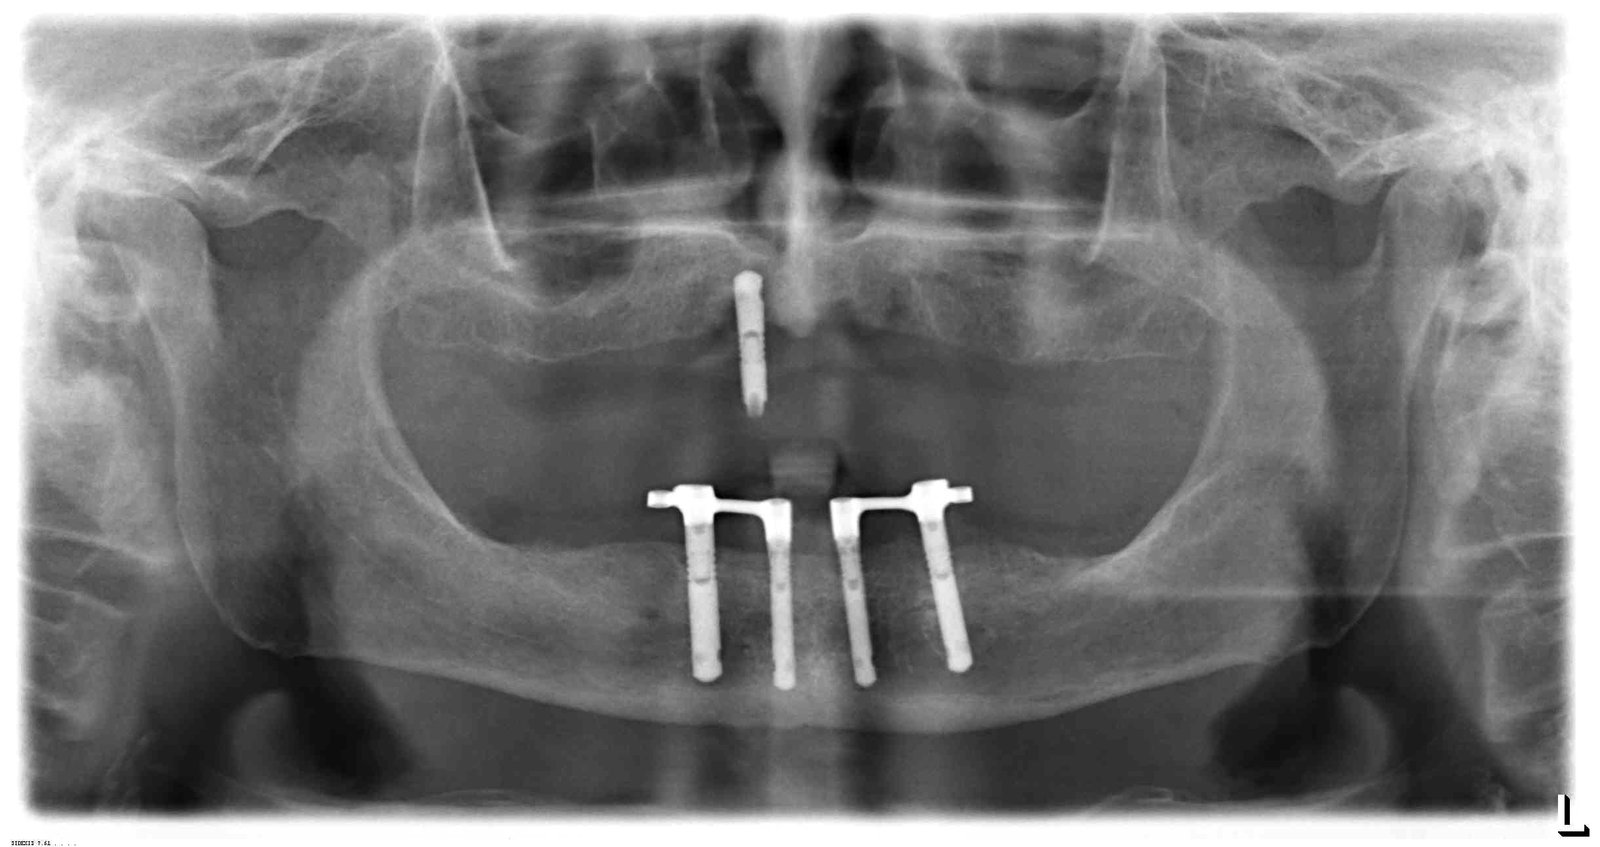

Buenos días detectives! Me podeis echar una mano con los implantes inferiores de este paciente? Se los pusieron hace muuuuuchos años impactándolos. Muchas gracias de antemano!